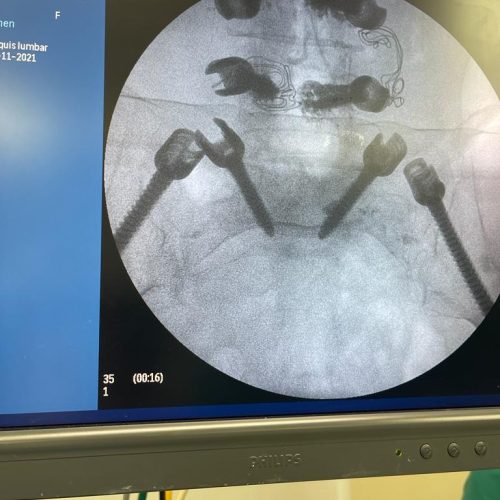

Fusión Vertebral (Cervical o Lumbosacra)

¿Qué es?

Es un procedimiento quirúrgico que busca estabilizar la columna vertebral uniendo de forma permanente dos o más vértebras. Se utilizan tornillos, barras y, en ocasiones, una caja intersomática con injerto óseo, para que las vértebras se fusionen en una sola unidad sólida.

¿Qué se logra?

- Estabilidad de la columna

- Reducción del dolor por movimiento excesivo

- Prevención de daño neurológico progresivo